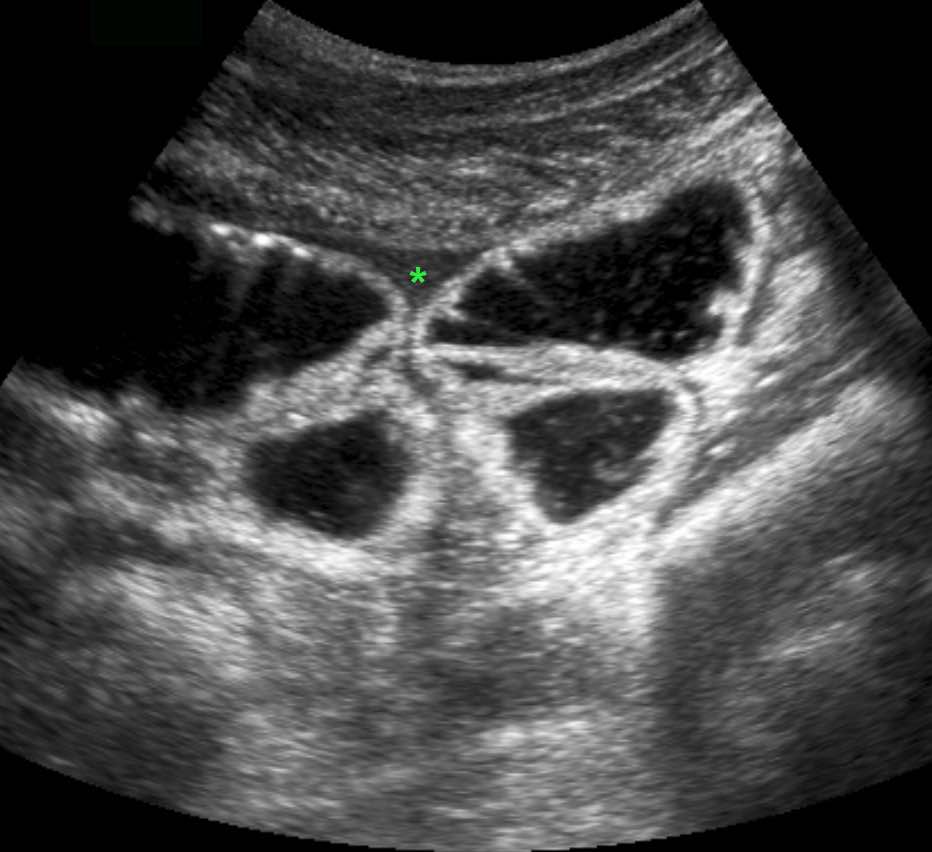

Hai cá nhân không có triệu chứng với ruột thừa kích thước lớn, chứa đầy phân nhưng không viêm, được minh họa qua siêu âm và CT.

Lưu ý sự vắng mặt hoàn toàn của mô mỡ viêm xung quanh ở cả hai trường hợp.